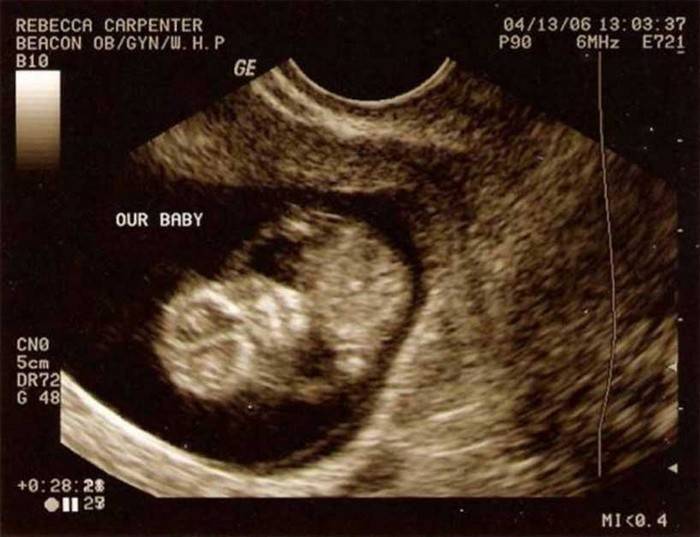

Ecografía

A las 11 semanas de gestación, una ecografía le permite evaluar el tamaño exacto del útero y la condición de su cuello, calcular la edad gestacional exacta y determinar la condición del feto. La ecografía en este período no se realiza según lo planeado, se requiere para confirmar cualquier problema o aclarar la condición del feto. Realizar exámenes de ultrasonido más frecuentes de lo esperado no amenaza la salud y el desarrollo del bebé.

¿Qué da un ultrasonido en este período? En primer lugar, aclara la edad gestacional y el tamaño del hogar, su estado, actividad y frecuencia cardíaca. La ecografía también da una idea de la estructura de muchos órganos del feto, determina la cantidad de líquido amniótico, el lugar de unión de la placenta y su estado. Si hay sospechas de ciertas patologías, la ecografía a las 11 semanas puede ayudar a identificar ciertas patologías o anomalías en el desarrollo del feto o la placenta.